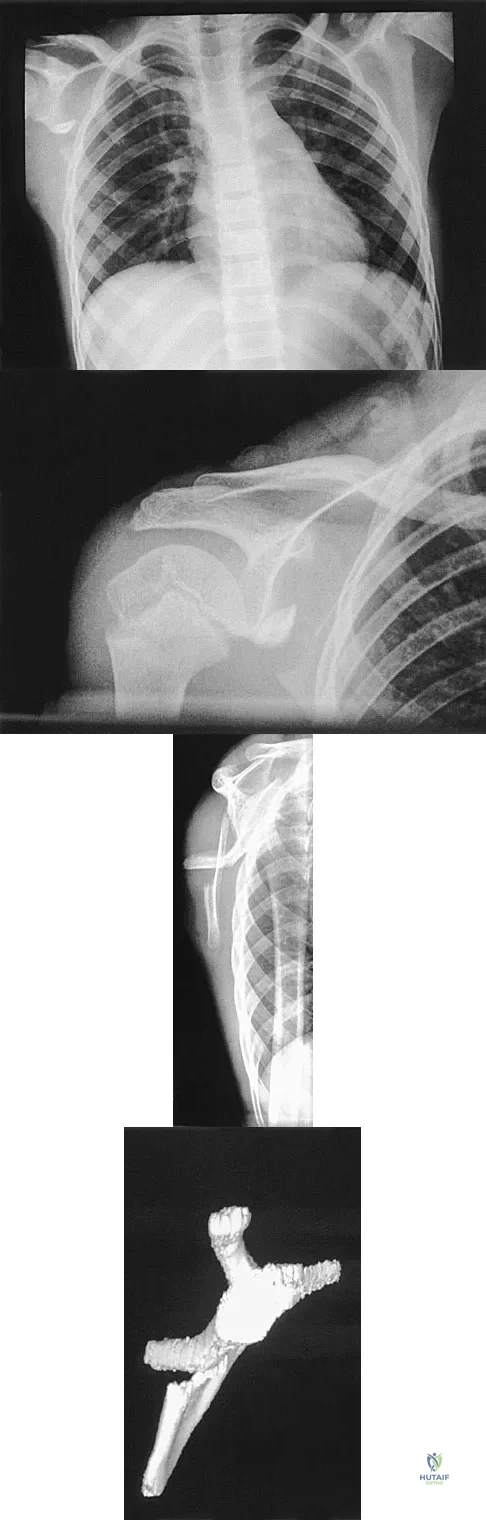

Question 32

A 12-year-old boy has severe left shoulder pain after being struck by an automobile. A chest radiograph, AP and lateral radiographs, and a CT scan with three-dimensional reconstruction of the scapula are shown in Figures 38a through 38d. Management should consist of

Explanation